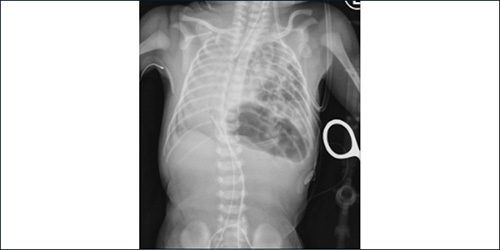

Pediatric pulmonologists from Columbia and Weill Cornell Medicine provide specialized testing and novel therapies for respiratory disorders in children of all ages. Through major centers in cystic fibrosis, asthma, sleep disorders, and aerodigestive and neuromuscular disorders, physicians at the Children's Hospital of New York partner with the patient and their parents to personalize treatment, including participation in clinical trials of the latest therapies, with the goal of helping young patients lead a normal and healthy childhood.

Pediatric Pulmonology